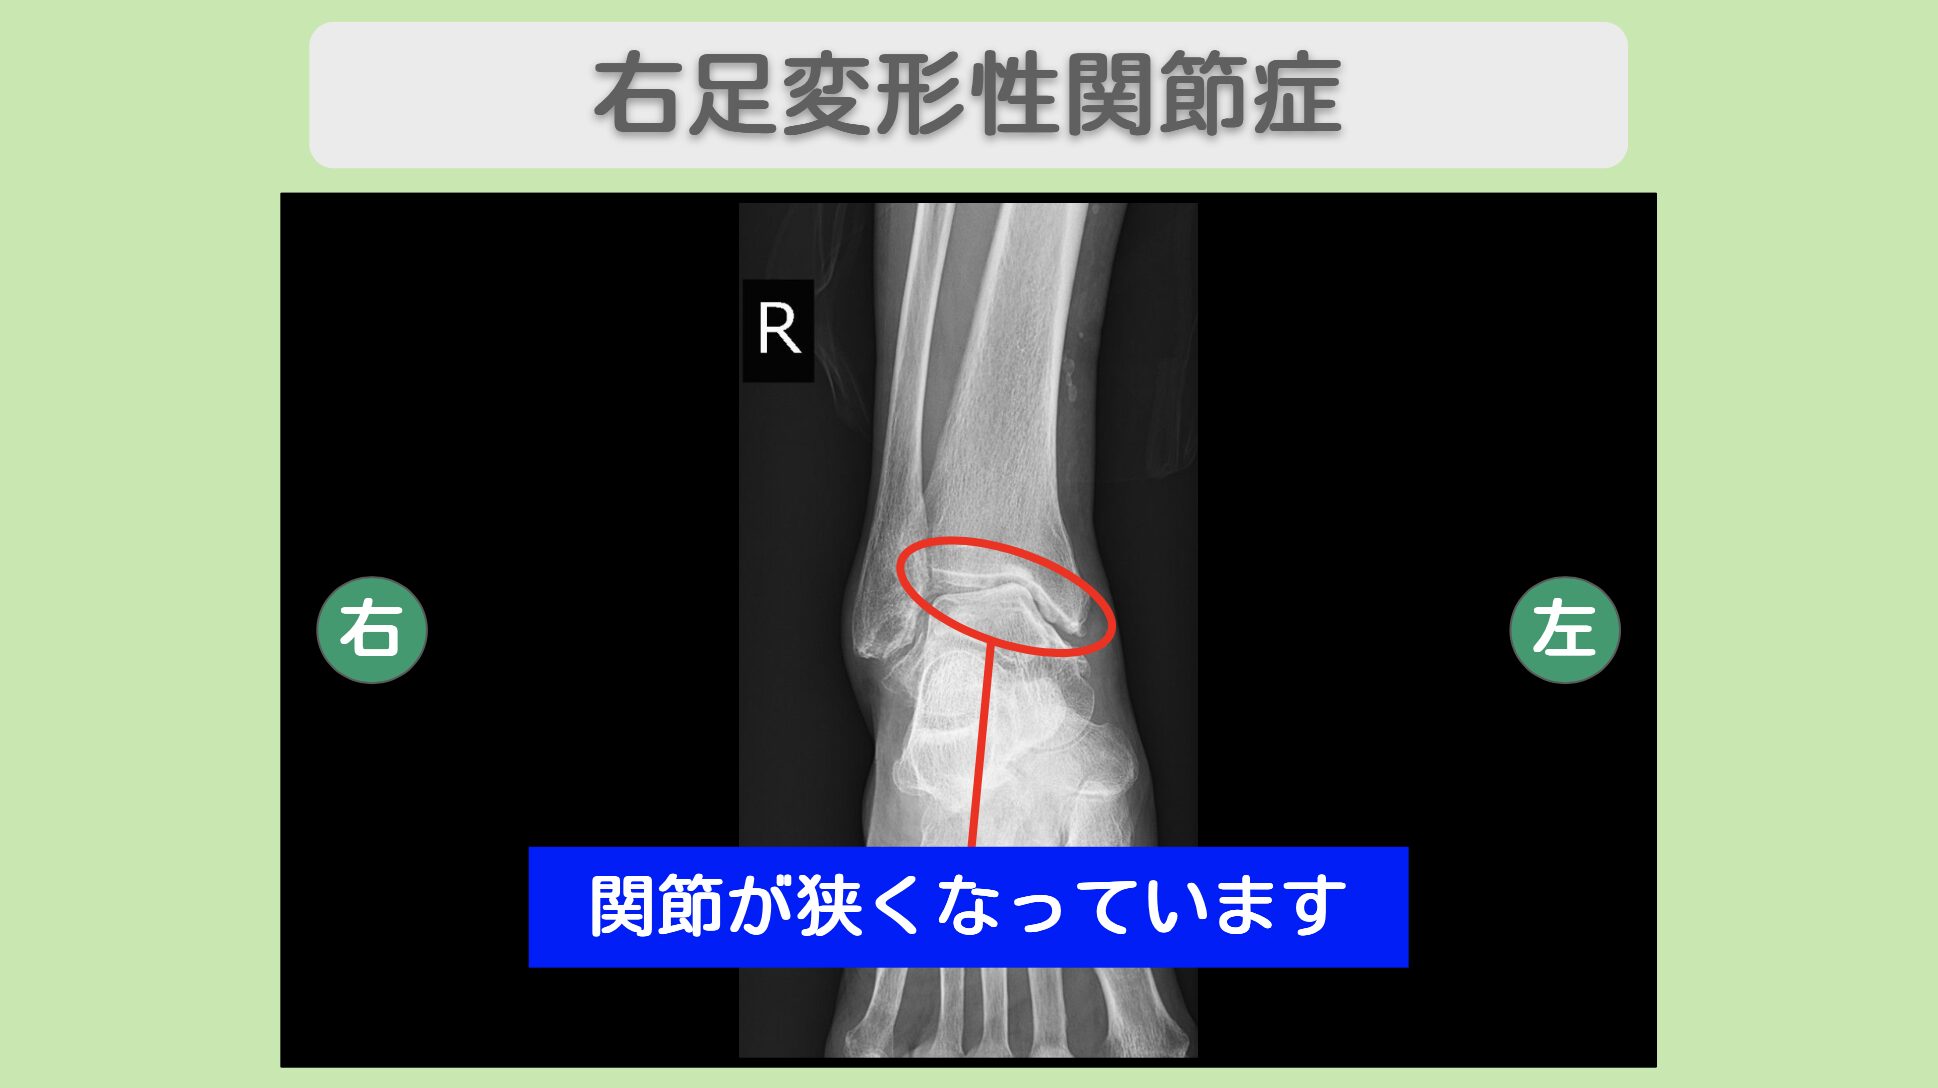

レントゲン所見

レントゲンにて関節の狭小化を認めます

レントゲン検査では、右股関節・右膝関節・右足関節のいずれにおいても軟骨のすり減りが確認されました。